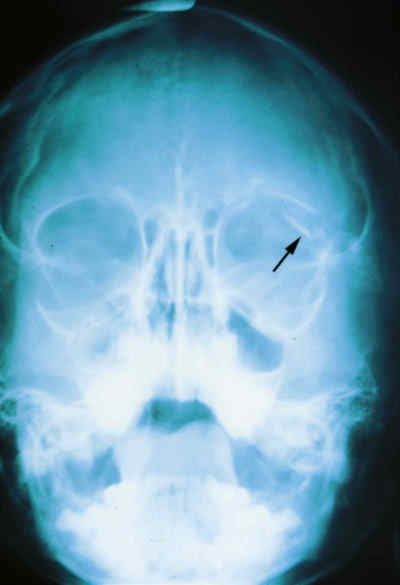

La utilización de Rayos X (figura 15) con proyecciones Caldwell, Waters, o las antero-posteriores pueden demostrarnos la presencia, pero no la localización, de un CEIO radiopaco y no detectará CEIO radiotransparentes, como la madera o el cristal. La ecografía nos ofrece una mejor localización del CEIO y es esencial para obtener información acerca de otros cambios estructurales como desprendimientos de retina o coroides. Al realizar esta exploración, han de tomarse precauciones para no comprimir el globo, sobretodo en los que presentan grandes heridas, y no producir prolapsos adicionales de su contenido. La ecografía con un estudio sistemático, con abordaje transversal y longitudinal puede determinar la localización del CEIO. La ultrasonografía biomicroscópica nos aporta algo más a la hora de diagnosticar cuerpos extraños ocultos o de polo anterior (123-125). La tomografía computerizada (TC) es el método diagnóstico de elección porque localiza y detecta CEIO radiopacos y radiotransparentes en 3 dimensiones. La TC tiene ciertas limitaciones y los CEIO metálicos crean artefactos significativos, que pueden dificultar la localización exacta. Esto puede ser un inconveniente a la hora de determinar si la localización de un CEIO es intrarretiniana o intraescleral. Asímismo la TC puede presentar problemas a la hora de identificar algunos CEIO de baja densidad, como la madera. Chacko, nos presenta en su artículo una interesante comparación entre la Tomografía Computerizada clásica (figura 16) y el TAC helicoidal (figura 17), demostrándose esta última más eficaz para la localización espacial de cuerpos extraños intraoculares o intraorbitarios (126).

63-16.jpg (11435 bytes)

Figura 16. Perdigón que pasa a través del ápex orbitario destrozando el nervio óptico.